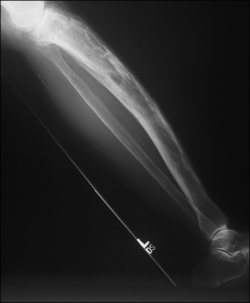

In Paget’s disease there is a marked increase in bone turnover in parts of the skeleton, resulting in the development of structurally weak abnormal bone, with an increased risk of pain, fracture, deformity, osteoarthritis of the large joints and deafness (ARMA 2007) (Fig. 20.7). Over the last few years a number of highly effective bisphosphonate treatments have been developed which can effectively suppress the symptoms and may prevent the development of complications (ARMA 2007).

image

Figure 20.7 Lateral radiograph of the lower extremity. Classic changes of Paget’s disease are present in the bowing deformity of the tibia, with marked cortical thickening and mixed lytic and sclerotic lesions. The fibula is spared.

With permission Hochberg MC (2008). Rheumatology edition Elsevier.